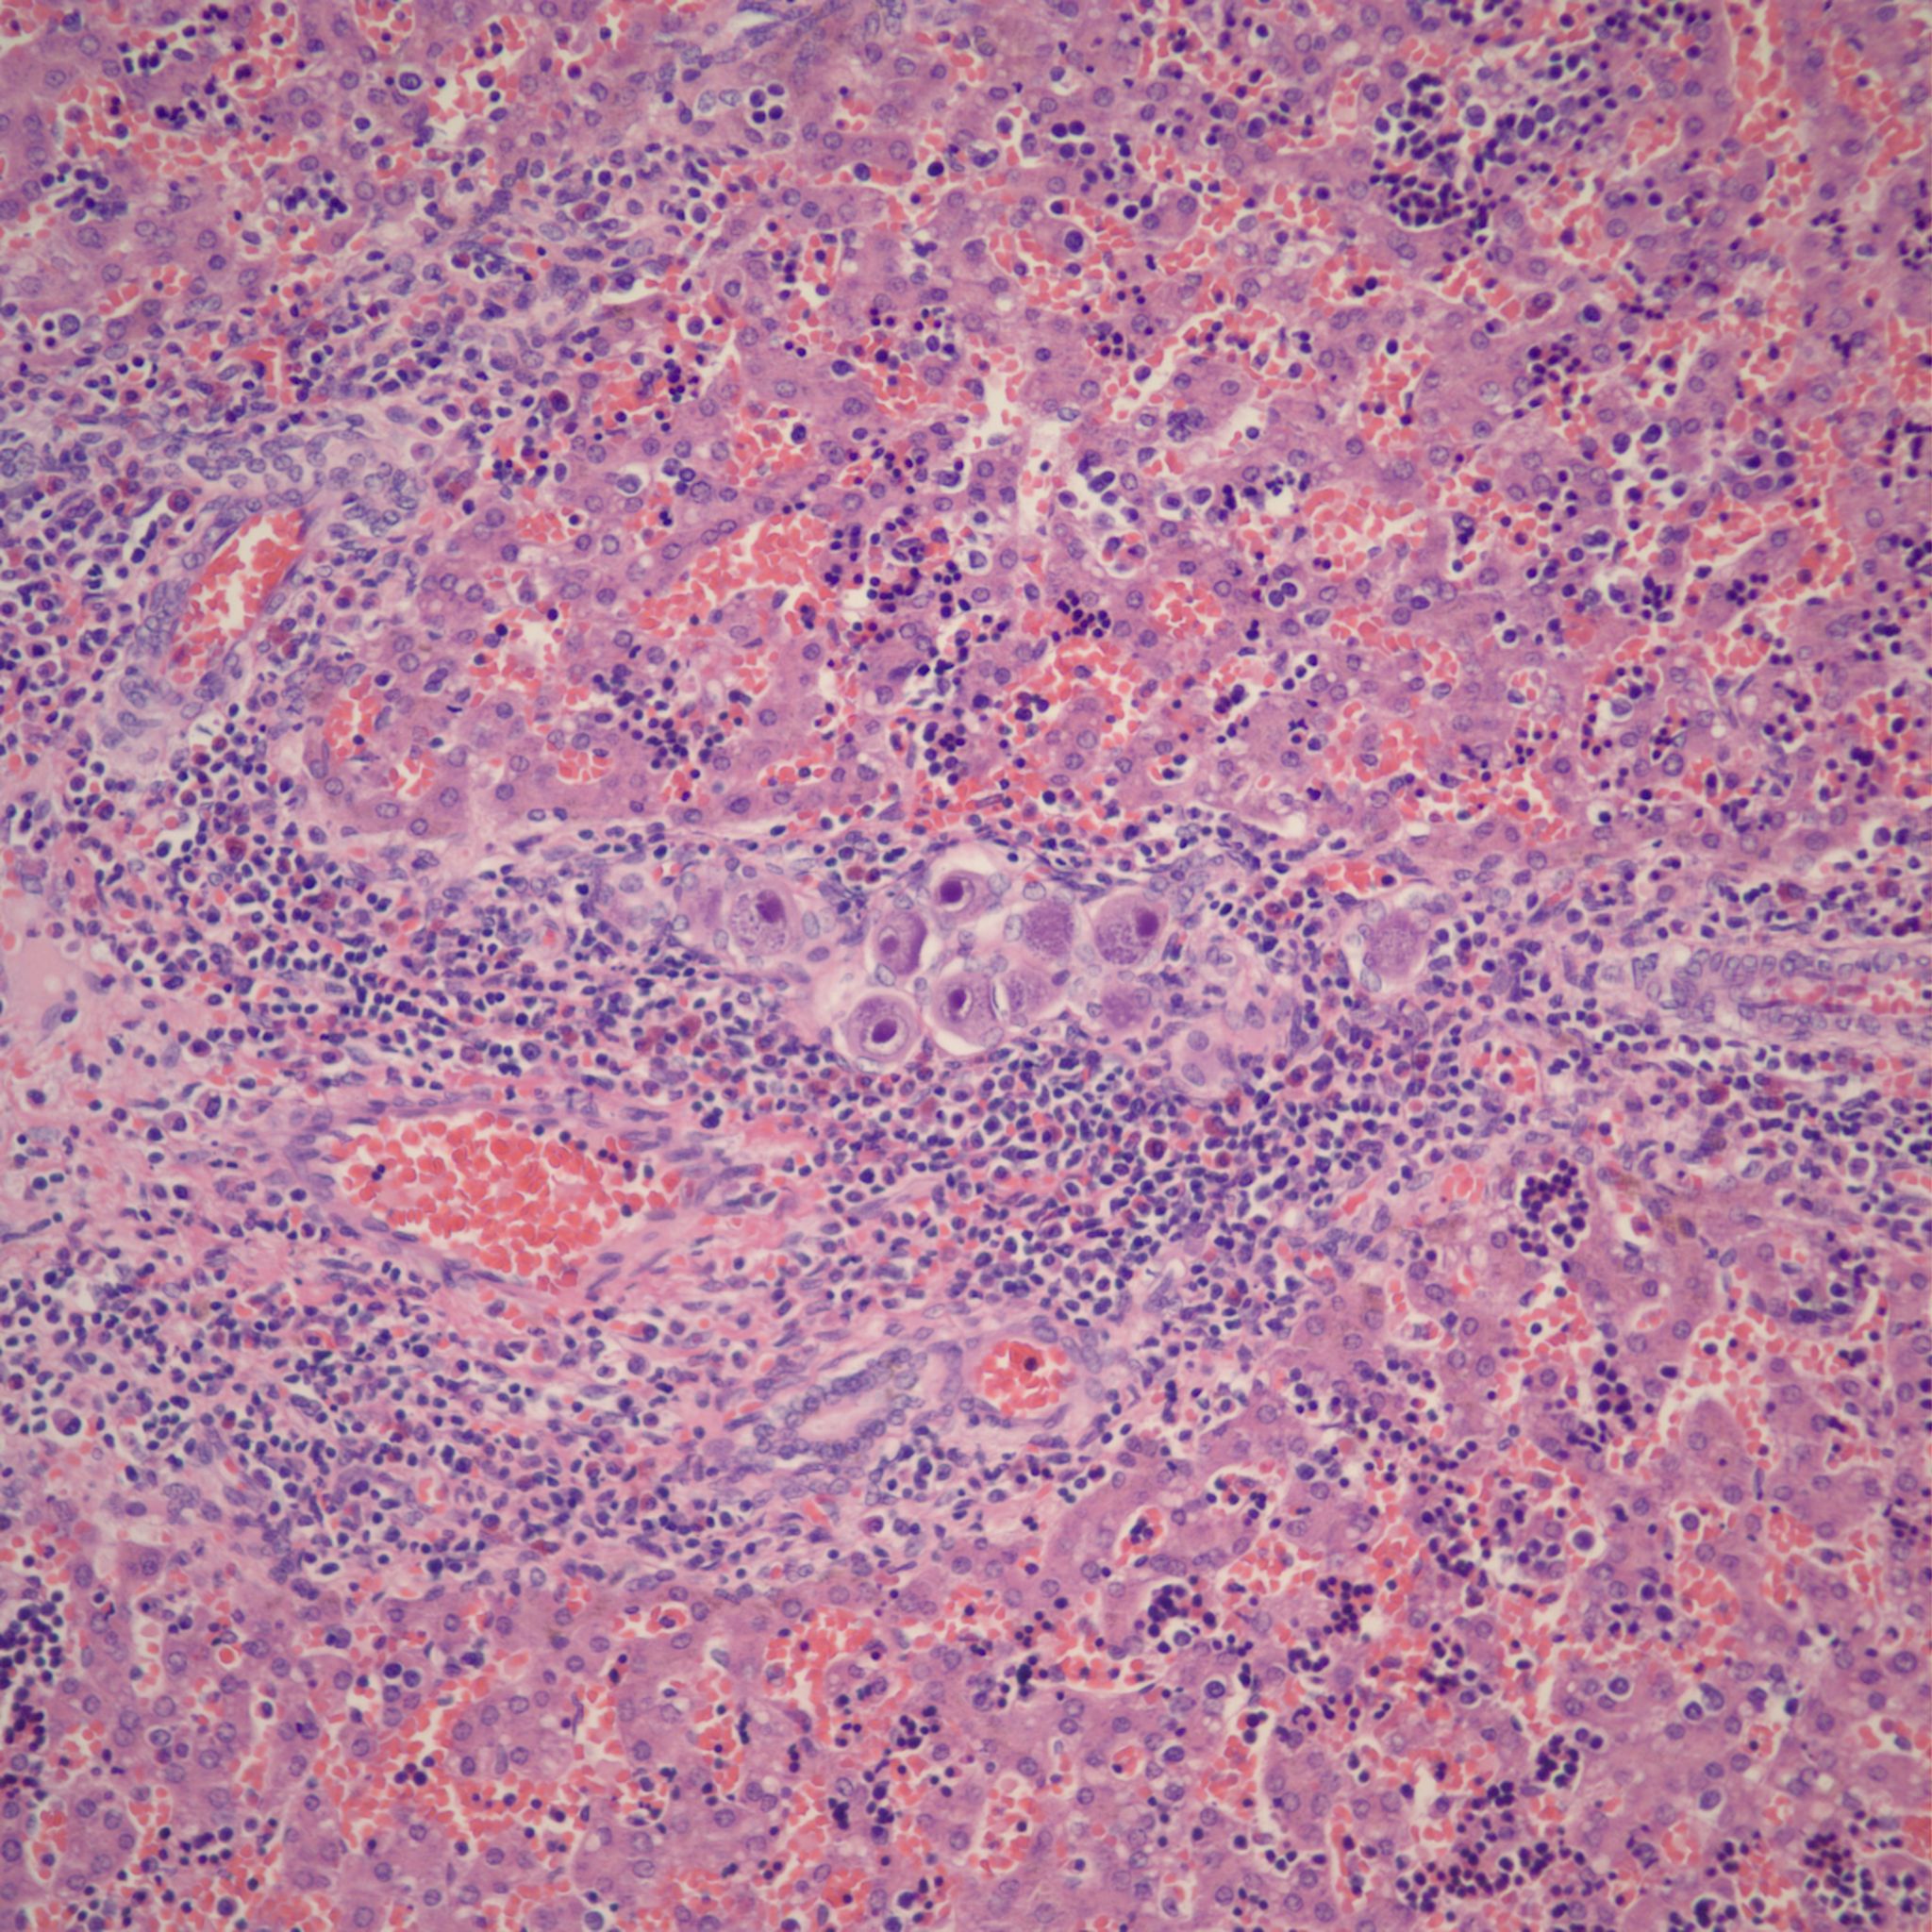

With pathologically increased erythropoiesis there is often grouping of cells at the same stage in erythropoietic development (fig 5a, b).